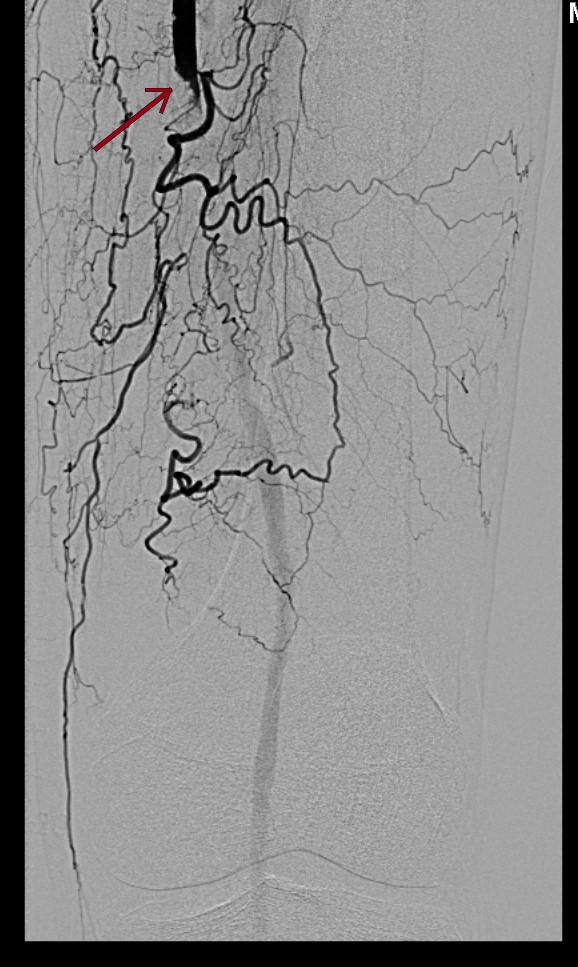

Как рассказали медики, к ним за помощью обратился пожилой мужчина, он жаловался на сильные боли в левой ноге при ходьбе даже на самые короткие расстояния, а также в состоянии покоя. Врачи обнаружили у 76-летнего пациента критическое сужение левой поверхностной бедренной артерии. Если бы мужчина еще немного затянул с походом в больницу, то развилась бы гангрена ноги, скорее всего, ее пришлось бы ампутировать.

Они провели пациенту высокотехнологичную малоинвазивную операцию по восстановлению проходимости артерии − баллонную ангиопластику и стентирование. После операции просвет артерии восстановился – пациенту удалось сохранить ногу. Более того, ходить он может теперь долго и без боли, а значит, человеку вернули активную полноценную жизнь.